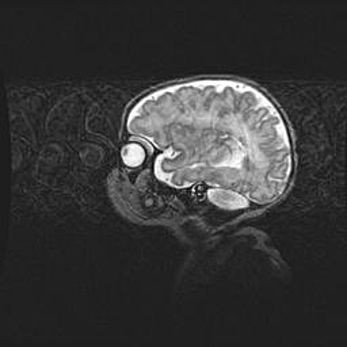

Церебральная ишемия II.

Возраст: 5 дней

Вес: 3400 г

Пол: женский

Окружность головы: 35 см

Срок гестации: 39 недель

Церебральная ишемия – это заболевание, характеризующееся недостаточностью (гипоксией) либо полным прекращением (аноксией) снабжения мозга кислородом по причине закупорки одного или нескольких сосудов. Это приводит к  что метаболическим расстройствам различной степени тяжести в тканях головного мозга, развитию коагуляционных некрозов и гибели нейронов.